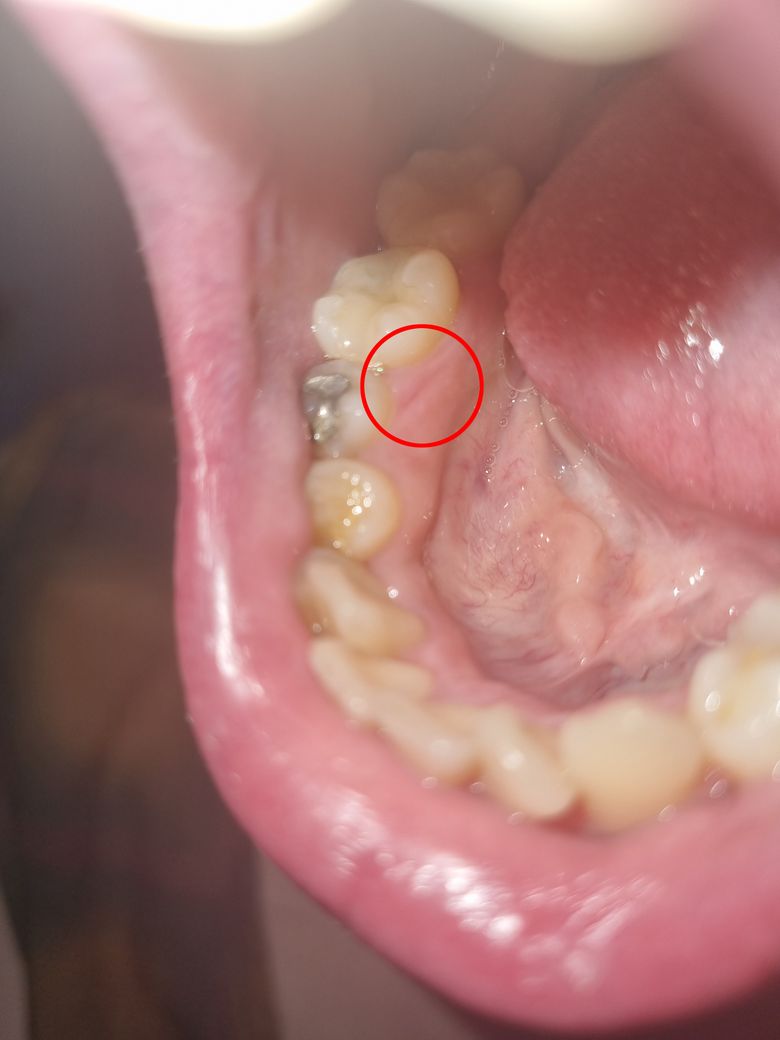

치간 칫솔 사용 하다가 긁혔는데 진료 받아 봐야 될까요?

어제 치간칫솔 사용하다가 긁혔는데 피가 조금 났는데....치과 가서 진료 받아 보아야 될까요?

아니면 연고 같은거 발라주어야 될까요?

• 1번 째 사진